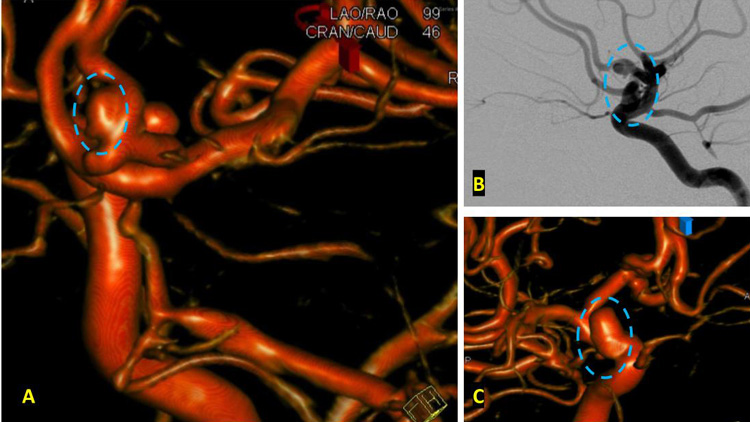

On admission, she presented as a GCS 3, was intubated, and stabilized hemodynamically in preparation for emergent catheter cerebral angiography, which revealed 2 discrete geographically located aneurysms – 1) Anterior Communicating and 2) Right ICA Supra-Clinoid Segment. (Figure 2.)

The Pattern of Hemorrhage was diffuse and generalized. On more careful analysis, however, there appeared to be focal hemorrhagic clot within the anterior inter-hemispheric fissure which raised greater suspicion for the Anterior Communicating Aneurysm as the source of hemorrhage. Although Acom Aneurysm was smaller, it’s irregular shape and eccentric “nipple” suggested potential rupture point. (Figure 3.)